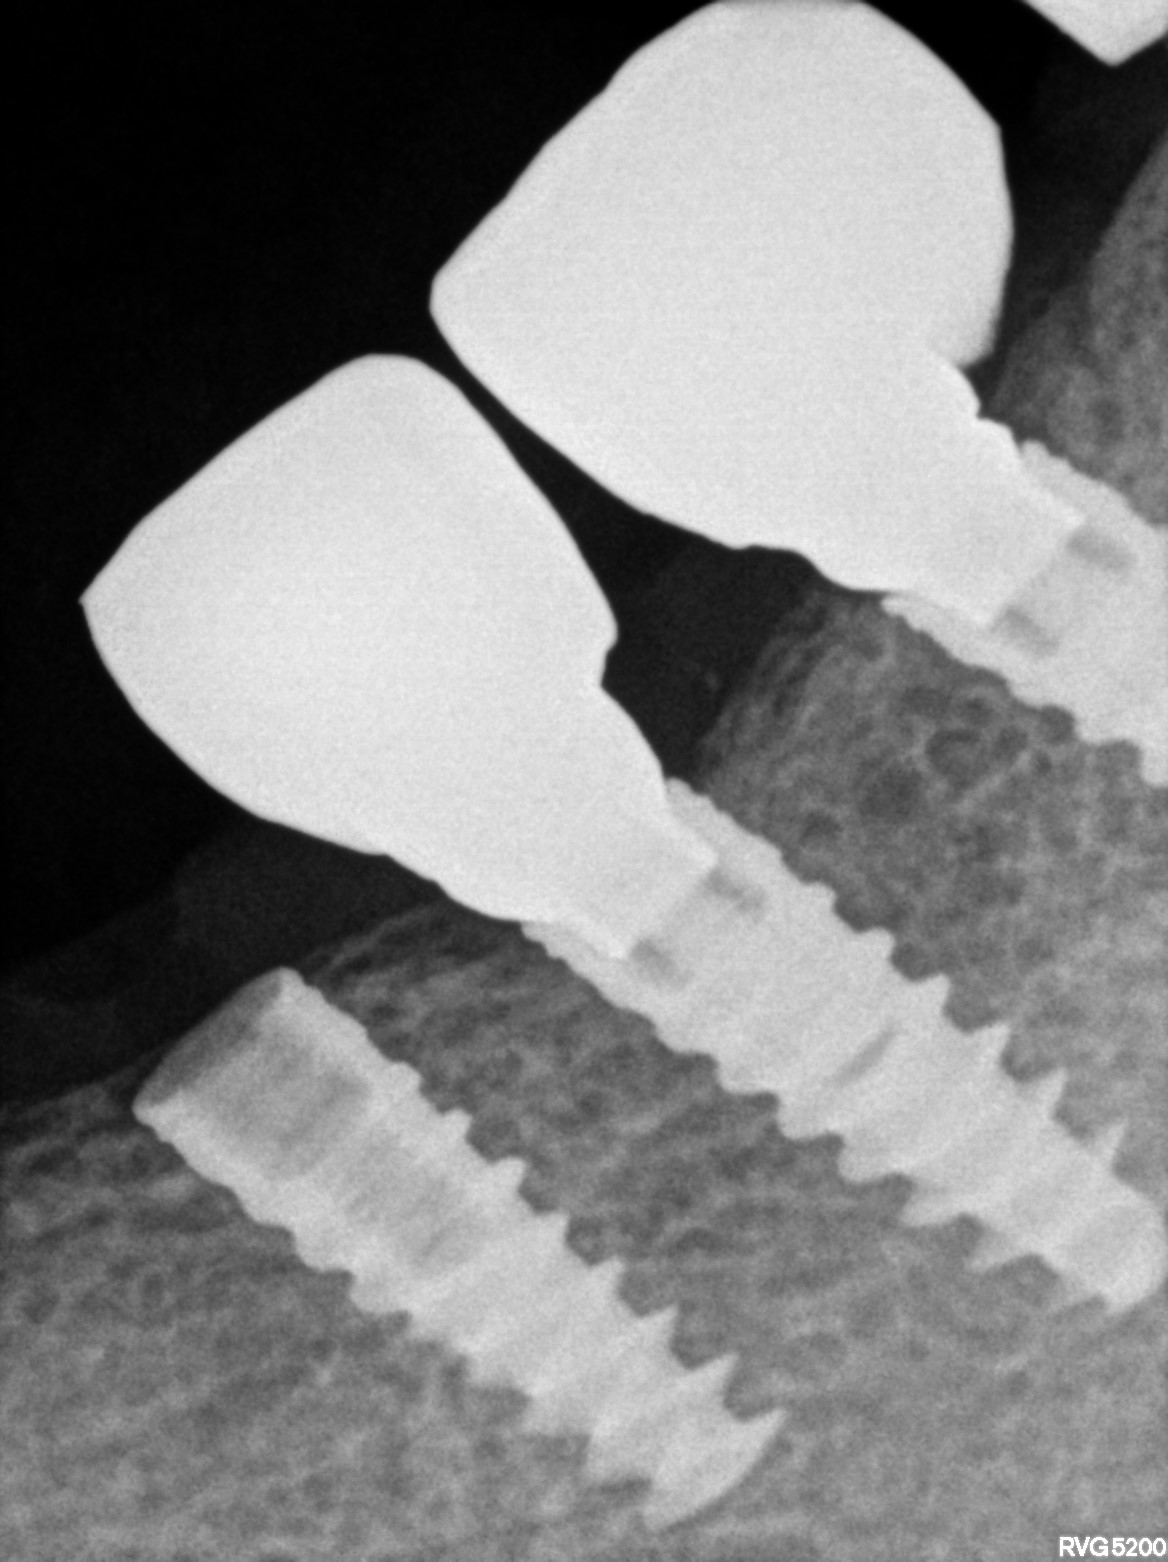

Dental Radiographs FHIR: DocumentReference · LOINC 24641-7

R73.jpg

24641-7